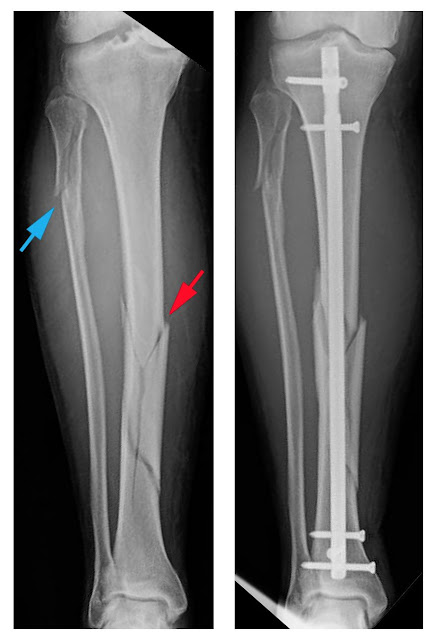

The doctor will like to know when and how the injury happened because he will be categorizing the possible fracture to the kind of injury you have sustained in your lower limb. X-rays will reveal the real score to your tibia and if there is incomplete fracture he may subject you to bone traction or realigning of your bone and then casting. If fragments show up on the x-ray, a more detailed diagnosis will be done with the use of MRI or CT scan so that every bit of the fractured bone including stress and hairline fractures could be identified.

The type of treatment can be dictated by the circumstances and the type of fracture that has occurred. The most conservative treatment would be the use of plaster fixation. For severe cases of tibial fractures, there could be operative reduction and rigid internal fixation that must be done to fix the broken tibial bone. Open reduction treatment which includes pinning, hyperextension with closed reduction and fixation in plaster is also another option